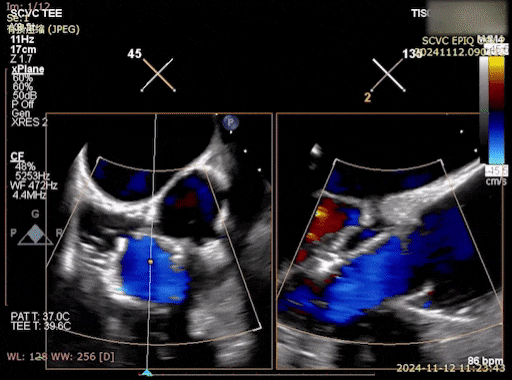

术后则通过超声心动图等手段对瓣膜功能、反流程度及右心负荷变化进行评估。

术后即刻反流消失,瓣膜稳定

在疗效方面,术后第1天随访显示患者心力衰竭症状明显缓解。影像学提示三尖瓣反流由术前重度显著改善至微量反流,右心系统容量及压力负荷均得到有效降低。同时,未观察到明显瓣周漏或瓣膜功能异常。